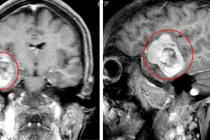

| Hình ảnh phim chụp trước và sau khi phẫu thuật lấy máu tụ. Ảnh BVCC |

Lúc vào bệnh viện trong tình trạng bệnh nhân hôn mê, Glassgow 10 điểm. Sau khi thăm khám, chụp cắt lớp vi tính sọ não, người bệnh được chẩn đoán chấn thương sọ não: chảy máu ngoài màng cứng thái dương trái. Người bệnh được phẫu thuật lấy máu tụ nội sọ, sau phẫu thuật được duy trì hồi sức sau mổ.